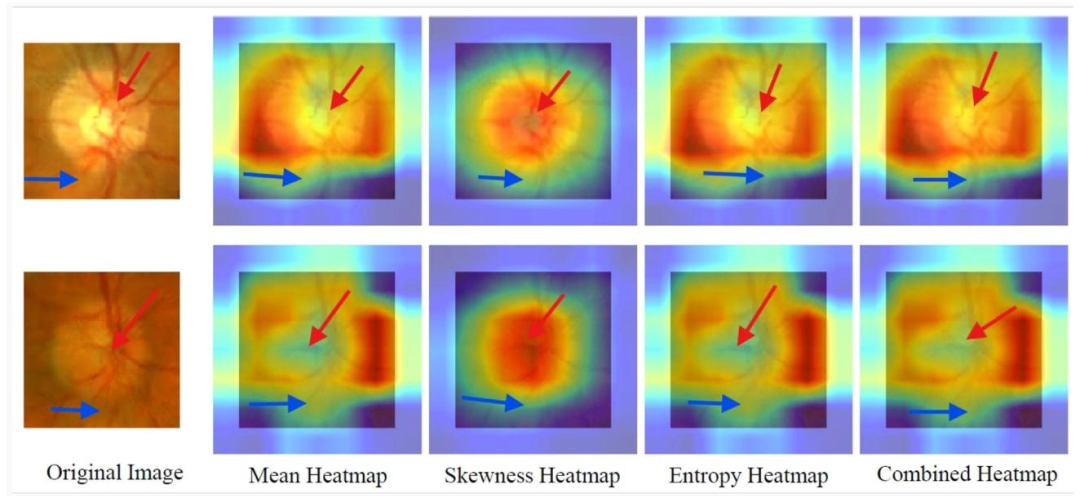

Fig. 8. SFMOV-based heatmap visualization showing a glaucoma image (row 1) and a normal image (row 2), both correctly classified, with model focus on clinically relevantoptic nerve regions. Red arrows indicate the macular zone, while blue ones are the transition zone with the non-macular area.

图8. 基于SFMOV的热图可视化,展示了一张青光眼图像(第1行)和一张正常图像(第2行),两者均被正确分类,模型聚焦于临床相关的视神经区域。红色箭头指示黄斑区,蓝色箭头指示与非黄斑区的过渡区。